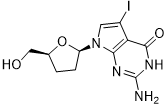

馬鞍山致研生物醫(yī)藥科技有限公司成立于馬鞍山市鄭浦港新區(qū)現(xiàn)代產(chǎn)業(yè)園。公司專(zhuān)注于生物小分子、醫(yī)藥中間體相關(guān)產(chǎn)品的研發(fā)和生產(chǎn),產(chǎn)品主要包括DNA亞磷酰胺單體、RNA亞磷酰胺單體、特殊單體以及按照客戶(hù)要求定制的RNA和DNA,并且公司提供定制合成等方面的研究服...

馬鞍山致研生物醫(yī)藥科技有限公司成立于馬鞍山市鄭浦港新區(qū)現(xiàn)代產(chǎn)業(yè)園。公司專(zhuān)注于生物小分子、醫(yī)藥中間體相關(guān)產(chǎn)品的研發(fā)和生產(chǎn),產(chǎn)品主要包括DNA亞磷酰胺單體、RNA亞磷酰胺單體、特殊單體以及按照客戶(hù)要求定制的RNA和DNA,并且公司提供定制合成等方面的研究服...